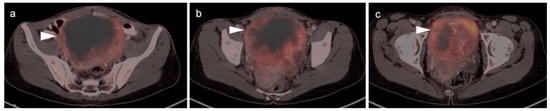

2.2. Ovarian Epithelial, Fallopian Tube and Primary Peritoneal Carcinoma

2.3. Uterine Neoplasms: Endometrial Carcinoma, Uterine Sarcoma and Leiomyoma

2.3.1. Endometrial Carcinoma